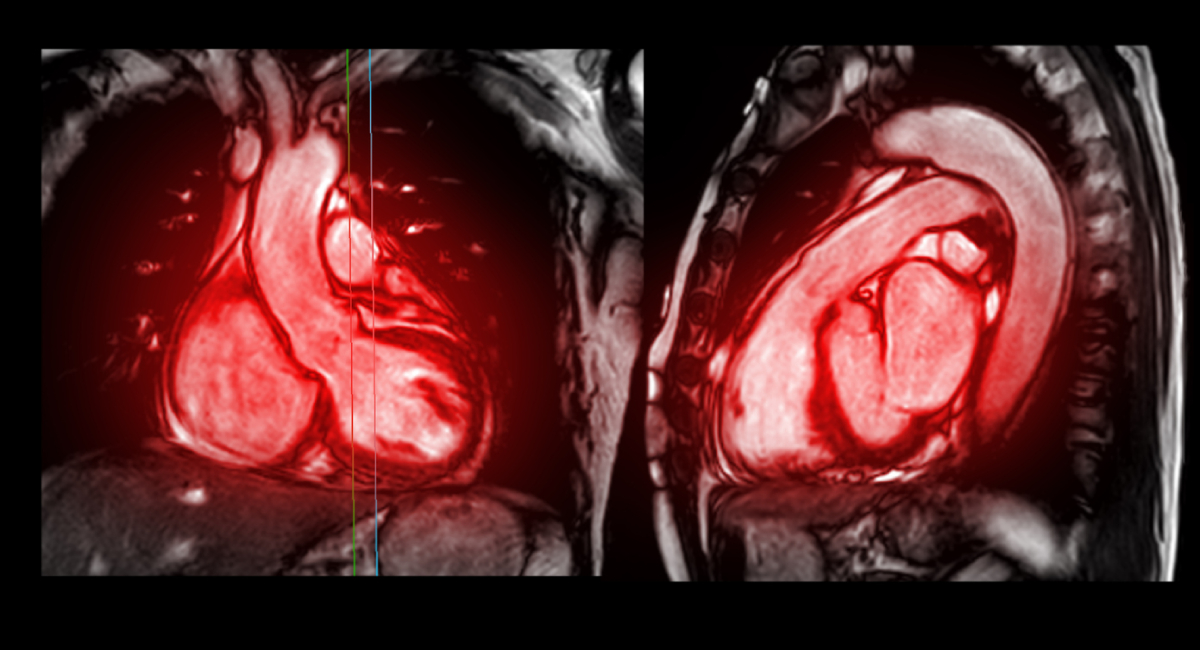

A pacemaker is a specialized device that uses electrical stimuli to adjust your heart’s beating when it is too slow or irregular. The pulse generator interacts positively with the heart’s chambers. If the heart rate … Read more